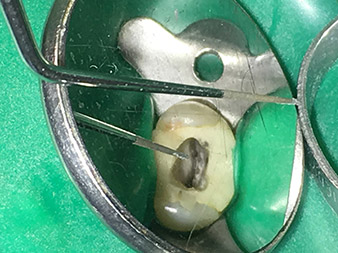

Efficient and atraumatic root canal treatment

Long-term conservation of dentition is the prime objective of modern endodontics.

Alongside efficient diagnostics and treatment methods, the use of the latest technical aids and instruments also makes an important contribution to successful patient care. Dr Shahrad Nouraie Ashtiani and his team at the practice in Bremen, Germany, treat up to ten endodontics cases a week. Patients’ desires for treatment which is as atraumatic as possible combined with good prognoses for success present a daily challenge for the dentist and oral surgery resident specializing in endodontics.

As an avid user of the expanded W&H instrument range for ultrasonic endodontics, Dr Nouraie Ashtiani is not only able to perform root canal treatments more efficiently but also to do so in a way which puts less strain on the patient. The dental expert masters even the most difficult of situations with ease. In a recent interview, the specialist in endodontics told us about the particular features which characterize the W&H instruments and mentioned possible risks which can arise in root canal treatment.

Dr. Nouraie: Yes, in my opinion. The tips allow you to work in a particularly atraumatic and minimally invasive manner. Among other steps, this applies to the exposure of the individual canal accesses, preparation of the cavity in the area of the pulp chamber, rounding off of the canal openings at the transition from the bottom of the chamber to the root canal and preparation of the coronal regions of the root canals.

It is also possible to activate the rinsing fluid in the root canal system. What’s more, it makes a range of special indications such as the revision of broken-off instruments and root posts possible.